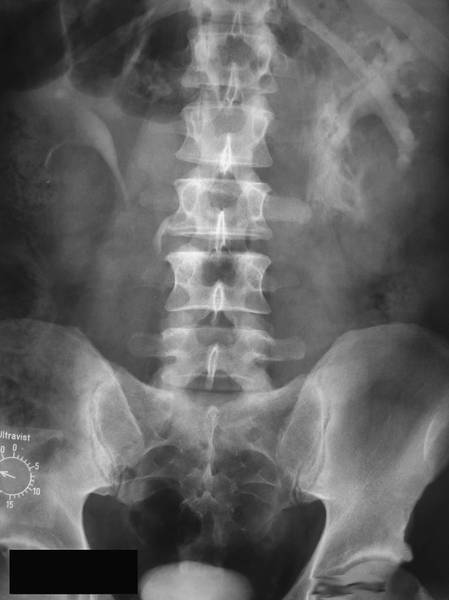

ЭКСКРЕТОРНАЯ УРОГРАФИЯ

Экскреторная урография (Binz, Roseno, 1929) основана на способности почек выделять контрастное вещество, введённое внутривенно (рис.).

Нормальная экскреторная урограмма.

Помимо определения функционального состояния почек, она позволяет получить представление о морфологическом строении мочевыводящих путей, но для этого функция почек должна быть удовлетворительной. По мере её снижения плотность тени контрастного вещества на рентгенограмме также уменьшается. Для проведения экскреторной урографии раствор контрастного вещества вводят в одну из периферических вен. В настоящее время применяют такие жидкие контрастные препараты, как амидотризоевая кислота℘, йогексол, йопромид и йодиксанол. При хорошей функциональной способности почек первую урограмму выполняют спустя 5–7 мин после введения контрастного вещества, у пациентов со сниженной функцией почек — спустя 10–12 мин. Следует обращать внимание на качество урограмм, степень заполнения контрастным веществом разных отделов ВМП, как с правой, так и с левой стороны. В зависимости от результатов первой урограммы последующие снимки выполняют на 15-й и 30-й мин. Если с одной стороны ВМП отчётливо выполнены контрастным веществом, а с другой тень контрастного вещества отсутствует или видна тень расширенных чашечек, то необходимы поздние снимки (через 1–2 ч).

При интерпретации урограмм следует обращать внимание на интенсивность теней паренхимы почек, их величину, форму и положение, начало выделения контрастного вещества в ЧЛС. Кроме того, нужно оценить плотность теней контрастного вещества в лоханках, чашечках и мочеточниках, наличие изменений в ВМП, время поступления контрастного вещества в мочевой пузырь и характер его заполнения. При экскреторной урографии тень рентгенопозитивного камня усиливается. Рентгенонегативный камень даёт дефект наполнения. При нарушении оттока мочи из почки всегда возникает расширение ВМП выше места окклюзии. Наиболее яркая иллюстрация этого — симптом Лихтенберга (рис.), который отмечают при камне мочеточника. Дилатация ЧЛС и мочеточника над камнем напоминает указующий перст, что дало второе название этому симптому — «симптом указательного пальца». Нужно помнить, что абсолютным доказательством камня мочеточника считают обнаружение симптома Лихтенберга на снимках в двух проекциях.